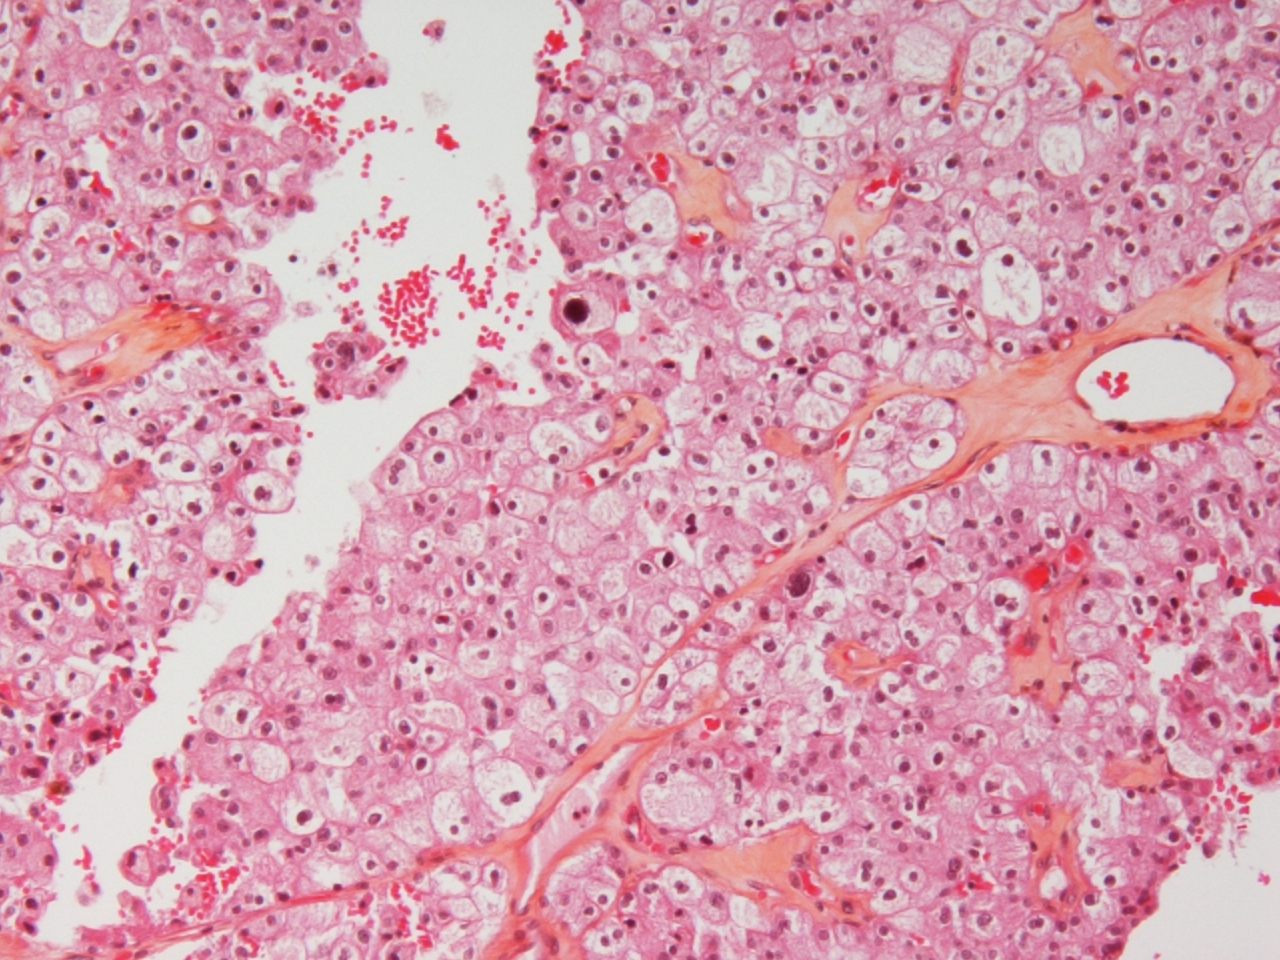

chromophobe RCC |

chromophobe |

just formal grading-I think it is chromophobe RCC |

chromophobe carcinoma